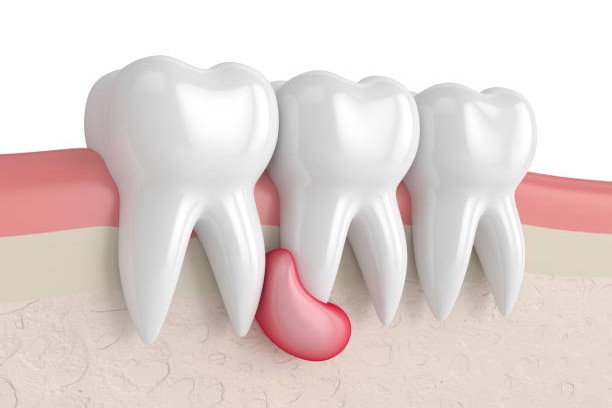

Cyst Removal

Precise surgical removal of oral cysts to protect jaw and surrounding tissues.